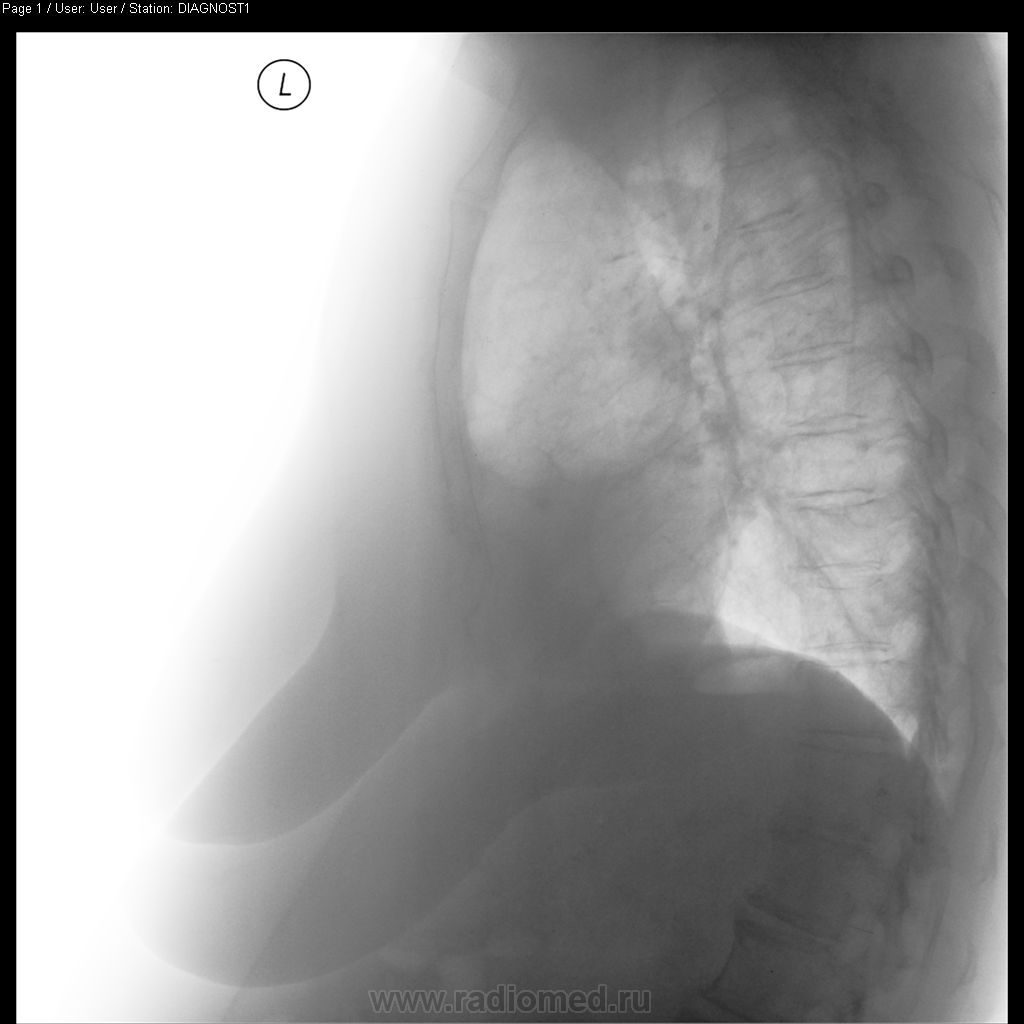

Женщина поступила в пульмонологическое отделение 14.10.2010 с жалобами на одышку, субфебрильную температуру в течние 2 недель, кашель с небольшим колчиеством слизстой мокроты. На момент поступления лейкоцитоз до 12х10`6, c небольшим палочкоядерным сдвигом. СОЭ - до 35

На момент 2-й рентгенографии (21.10.2010) - анализы в норме, кроме СОЭ (~30). Кашель субъективно стал меньше.

Что бы Вы думали по данным рентгенограмам и какая была бы ваша дальнейшая тактика.

Пневмония в S10 слева разрешилась, корни - не очень (лимфоузлы - сомневаюсь), справа в кардио-диафрагмальном синусе - интересные "спайки?" По возможности (и при наличие жалоб - как понял, самочувствие улучшилось) сделать бы КТ (если не жалко)...

В смысле, избыточная жировая клетчатка в левом кардио-диафрагмальном углу. Либо, менее вероятно, но всё же - осумкованный выпот.

Кстати, абдомино-медиастинальная липома - вероятна справа (левый кардиодиафрагмальный синус как раз "остренький").

Совсем забыл про исследование что выложил :) Вообщим, прямоугольная тень в проекции сердца - это хорошо развитая жировая клетчатка (причем развита с обеих сторон, чуть больше слева). У нас принято это назвать кардио-диафрагмальными липомами, но это никакие не липомы, просто - жир (жировые подушки как их обзывают зарубежом - "fat pad"). За счет этого у больной есть небольшие субсегментарные ателектазы с обеих сторон в S5 (веротяно за счет длительной компрессии). Также есть признаки хрон. бронхита. (утолщение стенок бронхов, их деформация).

Больной выполнил КТ (так как архива у нас предыдущего нет, и мне не очень нравились корни). Оказалось, что все в принципе нормально (к сожалению не мого тогда выложить видеоролик КТ - не было доступно). Постараюсь выложить в скором времени.

Если есть какие вопросы по скиалогии на данных снимках - спрашивайте. По мере сил, покажу за счет чего формируется каждая из теней.